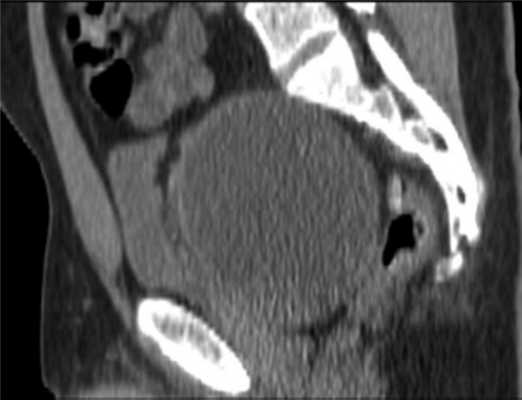

Считает себя больным с января 2011 г., когда появились болезненные ощущения в нижних отделах живота и промежности. С марта 2011 г. стал отмечать усиление боли, по поводу чего обратился в одну из городских клиник Москвы, где выявили опухоль малого таза (рис. 1).

Рис. 1. МР-томограмма малого таза. Опухоль малого таза.

По данным магнитно-резонансной томографии (МРТ) от 10.02.2012, в полости малого таза пресакрально располагается опухоль размером 9,2×9×7 см. Верхний полюс ее на уровне тела S I позвонка, распространяется в параректальную клетчатку, тесно прилежит к прямой кишке, оттесняя ее влево (граница прослеживается). Нельзя исключить прорастание в кишку, стенки прямой кишки отечны. Опухоль прилежит к семенным пузырькам и предстательной железе (граница прослеживается); мочевой пузырь оттеснен кпереди и кверху; верхний полюс опухоли расположен между грушевидными мышцами, прилежит к передней поверхности крестца и копчика (граница прослеживается), нижний полюс опухоли расположен между волокнами мышцы, поднимающей задний проход; нижние ягодичные сосуды справа оттеснены кпереди, тесно прилежат к опухоли на протяжении 3 см (рис. 2).

Рис. 2. МР-томограммы малого таза. Пресакрально располагается опухоль размером 9,2×9×7 см. а — сагиттальный срез; б — фронтальный срез.